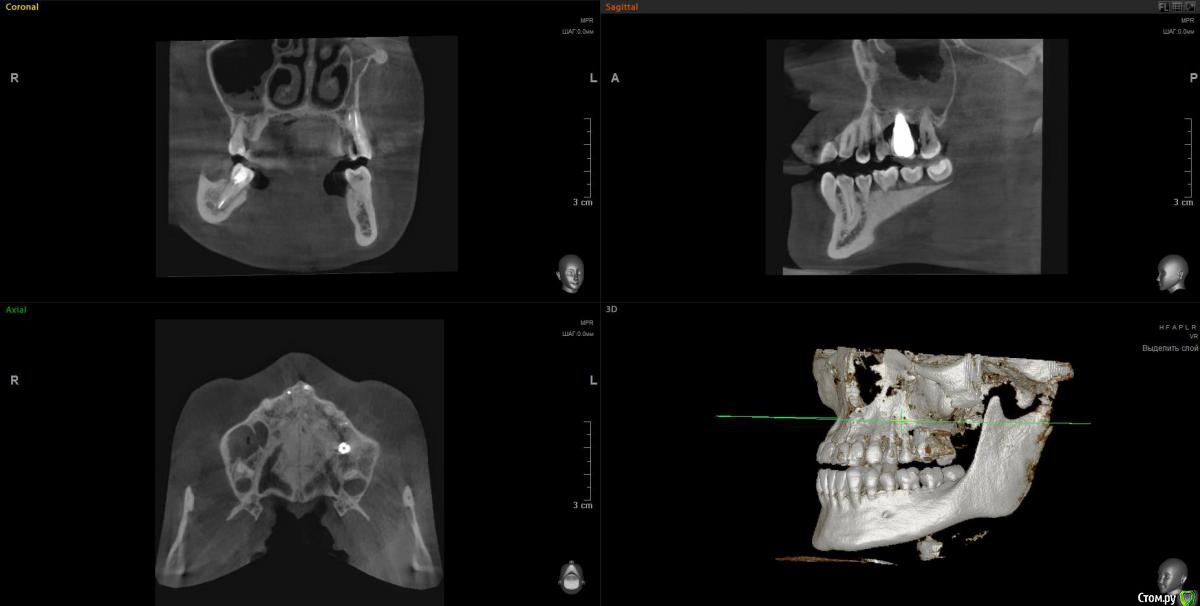

Lunar Опубликовано 8 апреля, 2020 Поделиться Опубликовано 8 апреля, 2020 Добрый день!Подскажите, пожалуйста, можно ли как-то разрулить ситуацию с левой стороной верхней челюсти..2014-2015гг - удаление 6 зуба, синуслифтинг, имплантация, протезирование. Все этапы отдельно. После синуслифтинга воспалилась пазуха и через n-ные промежутки времени делает это до сих пор и вот прямо сейчас в том числе (3 или 4ю неделю не могу с ней совладать). Ранее антибиотики решили вопрос с носовыми кровотечениями, но с остальной симптоматикой помогают лишь временно. Вместе с пазухой болит 7 зуб (из-за нее, или пазуха из-за зуба - один из вопросов..). Пару недель назад на десне над 7ой образовалось воспаление (гнойник). Сейчас десна поджила, зуб ноет тише, болит уже не половина головы, а только в районе пазухи, температура перестала повышаться. За 5 лет болеть все начинало от переохлаждения, само по себе и после стоматологических манипуляций в области импланта и 7 (раза 3 или 4 делали контакты, тк в промежутки все время все забивается).Тк прижало весьма не вовремя, почти все стоматологии закрыты, я буду очень благодарна, если сможете посмотреть снимки ( скрины кт после удаления, после синус лифтинга и недельной давности, только не уверена в правильности проекций..) и сориентировать по вопросам:1. Воспаление в пазухе связано ли с зубами?2. Депульпирование или удаление 7 зуба поможет снять воспаление? если это возможно определить по снимкам.. 3. Можно ли как-то исправить ситуацию в области импланта, в плане того, что заменить царь-коронку на что-то более компактное, чтобы оно начиналось не в складке, а поближе к остальным зубам? Удалять ли имеющийся?. Попробовать повторно нарастить кость и/или десну.. или только менять коронку, чтобы создать нормальный контакт между зубами, снять воспаление, и можно было бы полноценно пользоваться этой многострадальной стороной..С какой стороны мне вообще к этому всему подступиться или лучше не трогать?Заранее большое спасибо! Ссылка на комментарий

Irouil Опубликовано 9 апреля, 2020 Поделиться Опубликовано 9 апреля, 2020 https://yadi.sk/d/FRKX9i80axqaUgПосмотрел я Ваше КТ. На мой взгляд, проблема чисто ЛОРовская, но... ЛОР врач может придраться к состоянию в полости рта и формально будет прав, поэтому Сначала проверить на витальность 7ку (вероятнее всего все же придётся депульпировать) Клинически осмотреть 5-ку (стоматологу терапевту). Потом к лору. Имплантат к пазухе вообще не имеет никакого отношения 1 Ссылка на комментарий

Irouil Опубликовано 10 апреля, 2020 Поделиться Опубликовано 10 апреля, 2020 Ну, вообще определённые вопросы к имплантату и по КТ, и по фото во рту есть. Но не связанные с пазухой Ссылка на комментарий

Irouil Опубликовано 10 апреля, 2020 Поделиться Опубликовано 10 апреля, 2020 На мой взгляд удалять имплантат пока не надо, но нужна очная консультация пародонтолога и новая коронка на имплантате Ссылка на комментарий